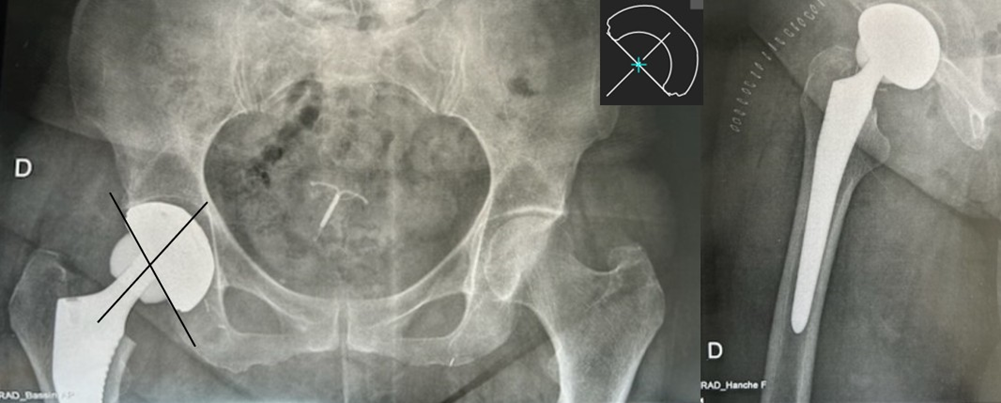

The immediate postoperative course was marked by squeaking. Postoperative radiographs showed a centered femoral head (Figure 1).

Figure 1: Postoperative anteroposterior pelvic and lateral right hip radiographs, 2013

The patient presented 11 years later with gradually worsening mechanical pain that had become disabling, with no triggering event. Hip range of motion was preserved. The surgical scar was non-inflammatory and the patient was afebrile. There was no clinical leg-length discrepancy, and the patient reported persistent squeaking since the immediate postoperative period, with no progression. Laboratory tests showed no inflammatory syndrome. Radiographs ?centricity with cranial migration

of the femoral head compared to the 2013 postoperative images (Figure 2). Wear measurements were obtained by adapting the method of Charnley et al. [4] used for polyethylene bearings, as no validated score exists for ceramic wear measurement on radiographs. CT confirmed cranial migration of the femoral head without clear fracture of the ceramic liner or head, and revealed femoral and acetabular periprosthetic granuloma (Figure 3).

Figure 2 : Anteroposterior pelvic and lateral right hip radiographs, 2024, showing 42?centricity of the prosthetic femoral head.